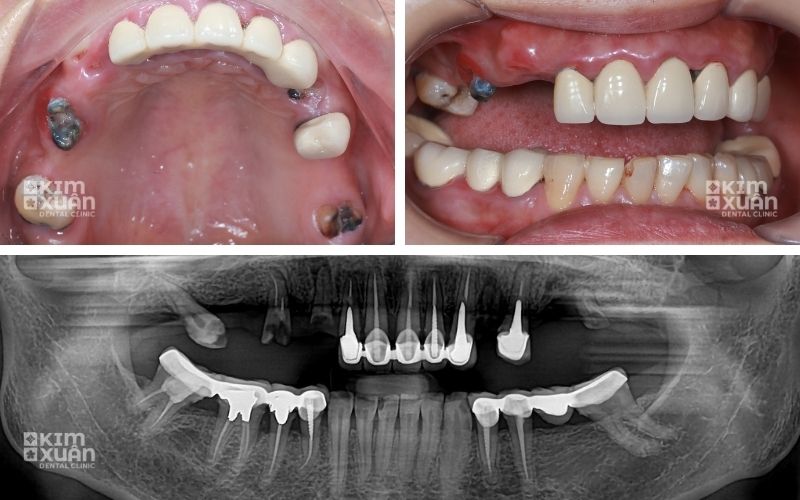

Khi phát hiện răng chỉ còn lại phần chân, người bệnh không nên chờ đợi hay để kéo dài tình trạng viêm nhiễm. Việc thăm khám nha khoa sớm, kết hợp chụp phim CT, giúp bác sĩ đánh giá chính xác mức độ tổn thương xương hàm và đưa ra hướng điều trị phù hợp.

Bước 1: Loại bỏ chân răng bị viêm

Ở giai đoạn này, bác sĩ sẽ tiến hành:

-

Lấy bỏ hoàn toàn phần chân răng đã hư tổn

Làm sạch mô viêm và ổ nhiễm khuẩn

Ngăn chặn sự lan rộng của vi khuẩn xuống xương hàm